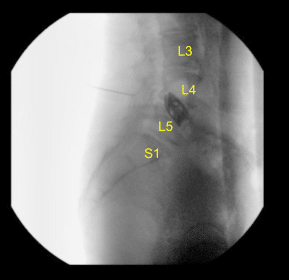

The lumbar region was prepped and draped in the usual sterile fashion and then employed a fluoroscopy to localize our incision, which was traced with an indelible marker on the midline of the lumbar region overlying the L4-L5 interspace. IV antibiotics were dosed and a call to order was completed.

We removed the soft tissue from the bone in a nontraumatic fashion and then applied the McCullough retractor system. Then the right-angled Gelpi retractors were used to hold the skin and muscle edges apart. We used fluoroscopy once again to localize our level of operation.